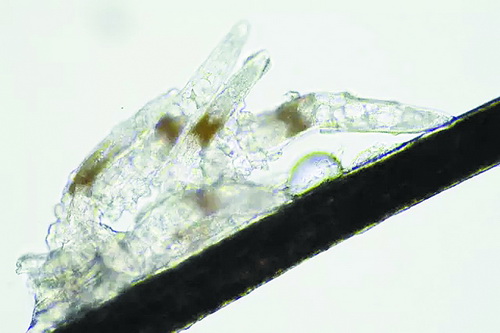

顯微鏡下長在睫毛中的螨蟲

冬天來了,氣溫降低,睫毛上的“隱形殺手”蠕形螨卻沒有要冬眠的意思。廈門大學附屬廈門眼科中心11月初開設蠕蟲性瞼緣炎門診以來,每天來查螨的市民都特別多,短短一個多月,已有近千人在顯微鏡下見到長期寄居在自己睫毛上,朝夕相處,卻素未謀面的蠕形螨。